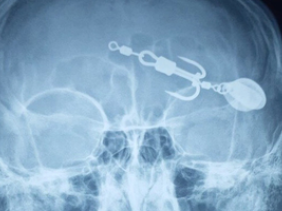

Phim chụp lưỡi câu móc vào mắt bệnh nhi. Ảnh: BVCC

Bệnh nhi V.T.T. (13 tuổi, trú tại huyện Tam Nông, Phú Thọ) được đưa đến cấp cứu tại Trung tâm Y tế huyện Thanh Sơn trong tình trạng tỉnh táo, rách da mi mắt trái, mắt trái bị dị vật găm sâu có nguy cơ làm tổn thương nhãn cầu. Dị vật là một chiếc móc câu 2 lưỡi.

Theo lời kể của người nhà, trước khi vào viện khoảng 1 tiếng, bệnh nhi đi xem bạn câu cá thì bị móc câu móc thấu mắt trái.